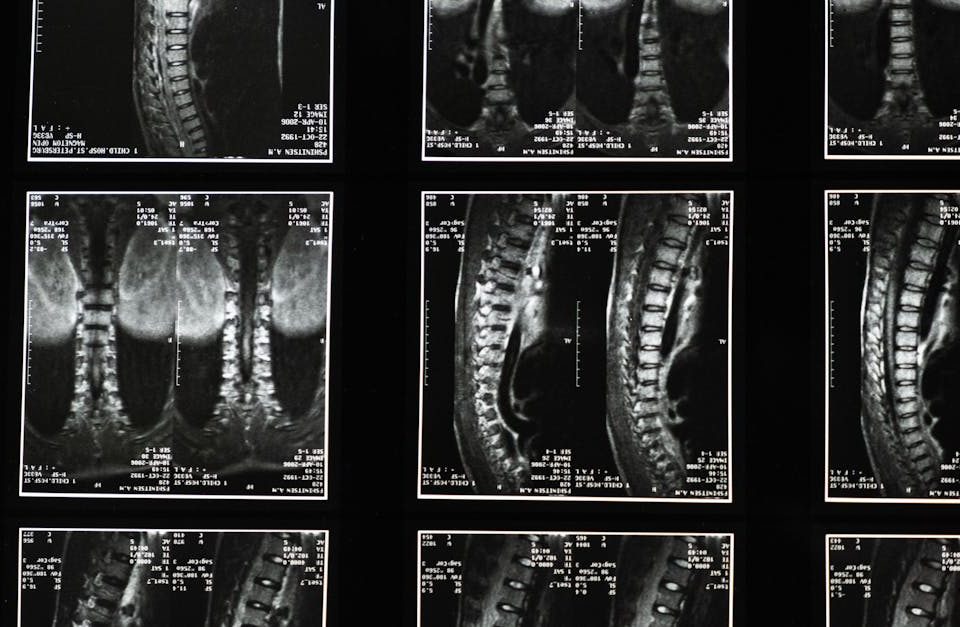

Sténose spinale lombaire : comment la décompression neurovertébrale peut aider

EN BREF La sténose spinale lombaire est une condition qui implique un rétrécissement du canal spinal, entraînant des douleurs et des symptômes variés. La décompression neurovertébrale […]

Hernie discale cervicale : comment la décompression neurovertébrale peut aider

EN BREF La hernie discale cervicale est une affection courante qui peut provoquer des douleurs cervicales sévères. La décompression neurovertébrale apparaît comme une solution non-invasive, particulièrement […]